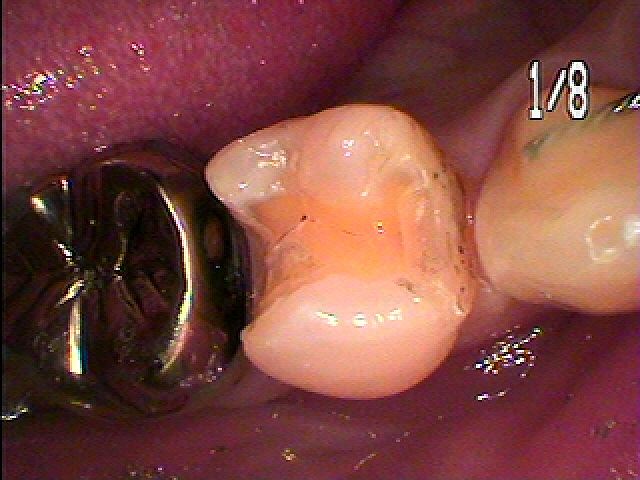

銀歯を外していきました

悪いところを除去していきました